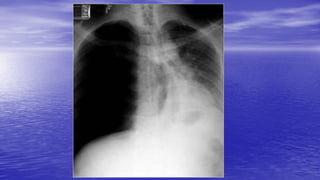

Tension pneumothorax

• The accumulation of air under pressure in the pleural space.

• An imminent danger is that the lung will collapse under the

pressure.

• In tension pneumothorax, air enters the pleural cavity and is

trapped there during expiration so the air pressure within the

thorax mounts higher than atmospheric pressure, compresses the

lung, may displace the mediastinum and its structures (including

the lung) toward the opposite side, and cause cardiopulmonary

impairment. Also called pressure pneumothorax,

Lesions acutely impairing ventilation:

• Tension pneumothorax - requires needle thoracostomy

followed by drainage.

• Flail chest - management involves ventilation.

• Haemothorax - will usually require intercostal drain

insertion.

• Pneumothorax - may require intercostal drain insertion.